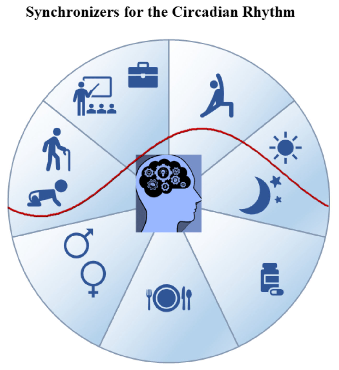

Factors influencing the rest-activity circadian rhythm and the sleep-wake cycle are mapped, encompassing light, melatonin, physical activity, and social timing cues.

Biological Rhythm and Chronotype: New Perspectives in Health.